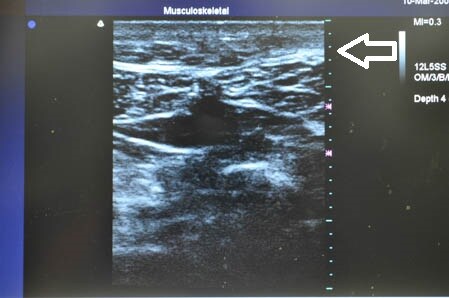

右の腰も見ておきましょう。

↓ ↓ ↓

医療関係者という患者様にも

ご満足いただける術中になりました。